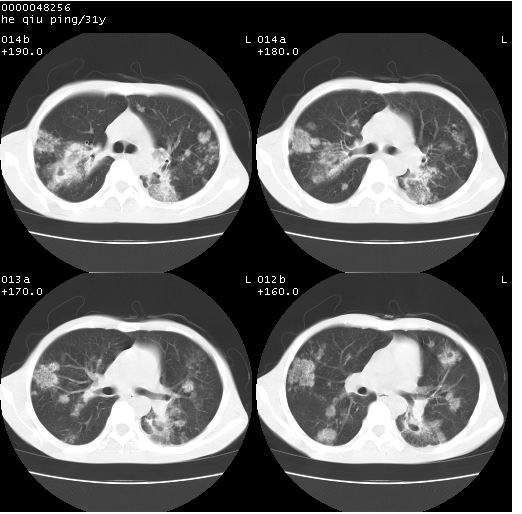

标题: CT13402:M,31Y。肺结核伴空洞形成? [打印本页]

标题: CT13402:M,31Y。肺结核伴空洞形成?

咳嗽半月余,消瘦体质,呼吸音弱。无其他病史。cr:肺转移瘤待。

双上肺多发空洞,双飞散在分布大小不一的片状结高密度影节状大片状高密度影。符合结合肉芽肿形成及空洞形成。

双侧弥漫性病变,双上叶尖后段、下叶北段见多个空洞,多见于结核感染。右中叶及双下叶斑片状,结节状影,考虑为肉芽肿形成及支气管播散。但由于患者消瘦体质,抵抗力低下,若继发感染,如金葡菌肺炎也有可能。

应该是比较典型肺结核伴空洞形成,下肺野播散。

考虑为:两肺结核伴多发空洞形成、支气管播散。

结核空洞并播散,玫瑰花簇征。

病灶多形性,有空洞形成。考虑肺结核伴空洞形成,两下肺支气管播散!